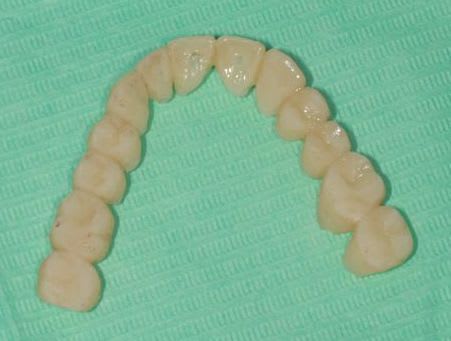

Ce matin pose de 8 ceramoceram (emax press) à la mandibule et pano de contrôle.

Je crois de plus en plus qu'extraire pour faire une MCI n'était pas le bon choix.